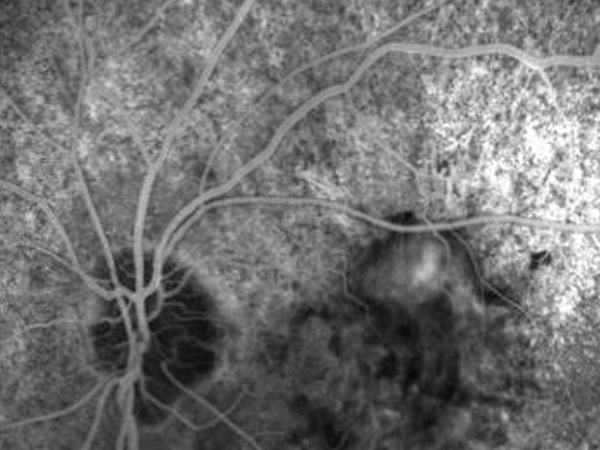

Fluorangiografia retinica

La fluorangiografia è un esame fondamentale per lo studio della retina. Si esegue iniettando in vena un mezzo di contrasto e scattando poi delle foto con uno strumento specifico. il mezzo di contrasto verrà poi eliminato con le urine. Serve anche come guida per il trattamento laser delle patologie retiniche. Infatti consente di mettere in evidenza le aree non irrorate e le lesioni provocate da nuovi vasi che si sviluppano a causa di carenza di ossigeno.